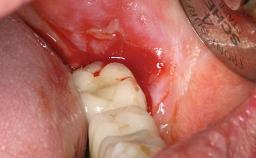

A male patient had lost teeth 11 and 22 as a result of a bicycle accident at age 14. In his adolescent years, a removable prosthesis had replaced the missing teeth. At age 21, the patient was referred by his dentist to the university clinic for treatment of the missing teeth 11 and 22 with implants. He was in good health and a nonsmoker. The absence of teeth 11 and 22 over many years had led to significant atrophy of the alveolar ridge, particularly at site 11. As a first step, the alveolar ridge was augmented using a block graft to replace the lost bone. A Straumann SP implant (diameter 4.1 mm, length 12 mm; Institut Straumann AG, Basel, Switzerland) and a Straumann Narrow Neck implant (length 10 mm) were inserted in the correct location and axial position at sites 11 and 22, respectively, six months later. After three months of healing and subsequent reentry, the patient returned to the referring dentist to receive the prosthetic restoration. The patient was seen again six months after the restoration had been placed. The frontal view showed a high smile line, an irregular gingival profile, and a bluish-gray tinge to implant crowns 11 and 22 compared to the natural dentition.